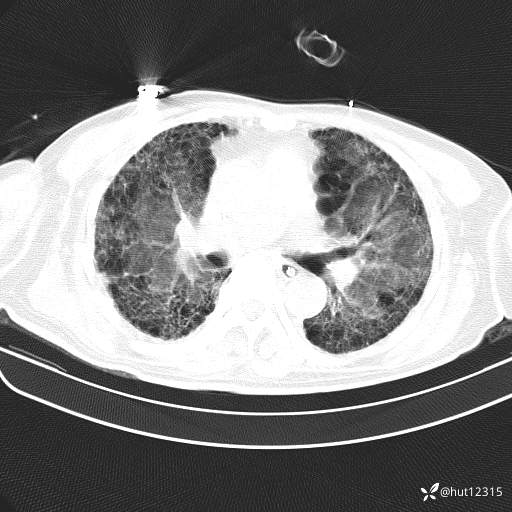

CT:肺纤维化并感染

2.特发性肺纤维化并重症肺炎,ARDS